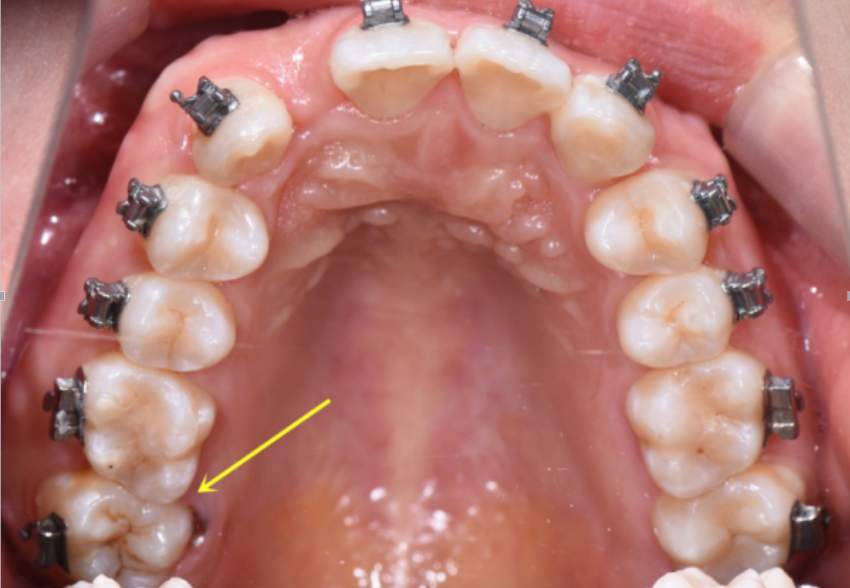

后牙锁合矫治一例----屈晓兵

一例安氏ii类ii分类伴双侧后牙正锁合病例分享

一例安氏ii类ii分类伴双侧后牙正锁合病例分享李望松